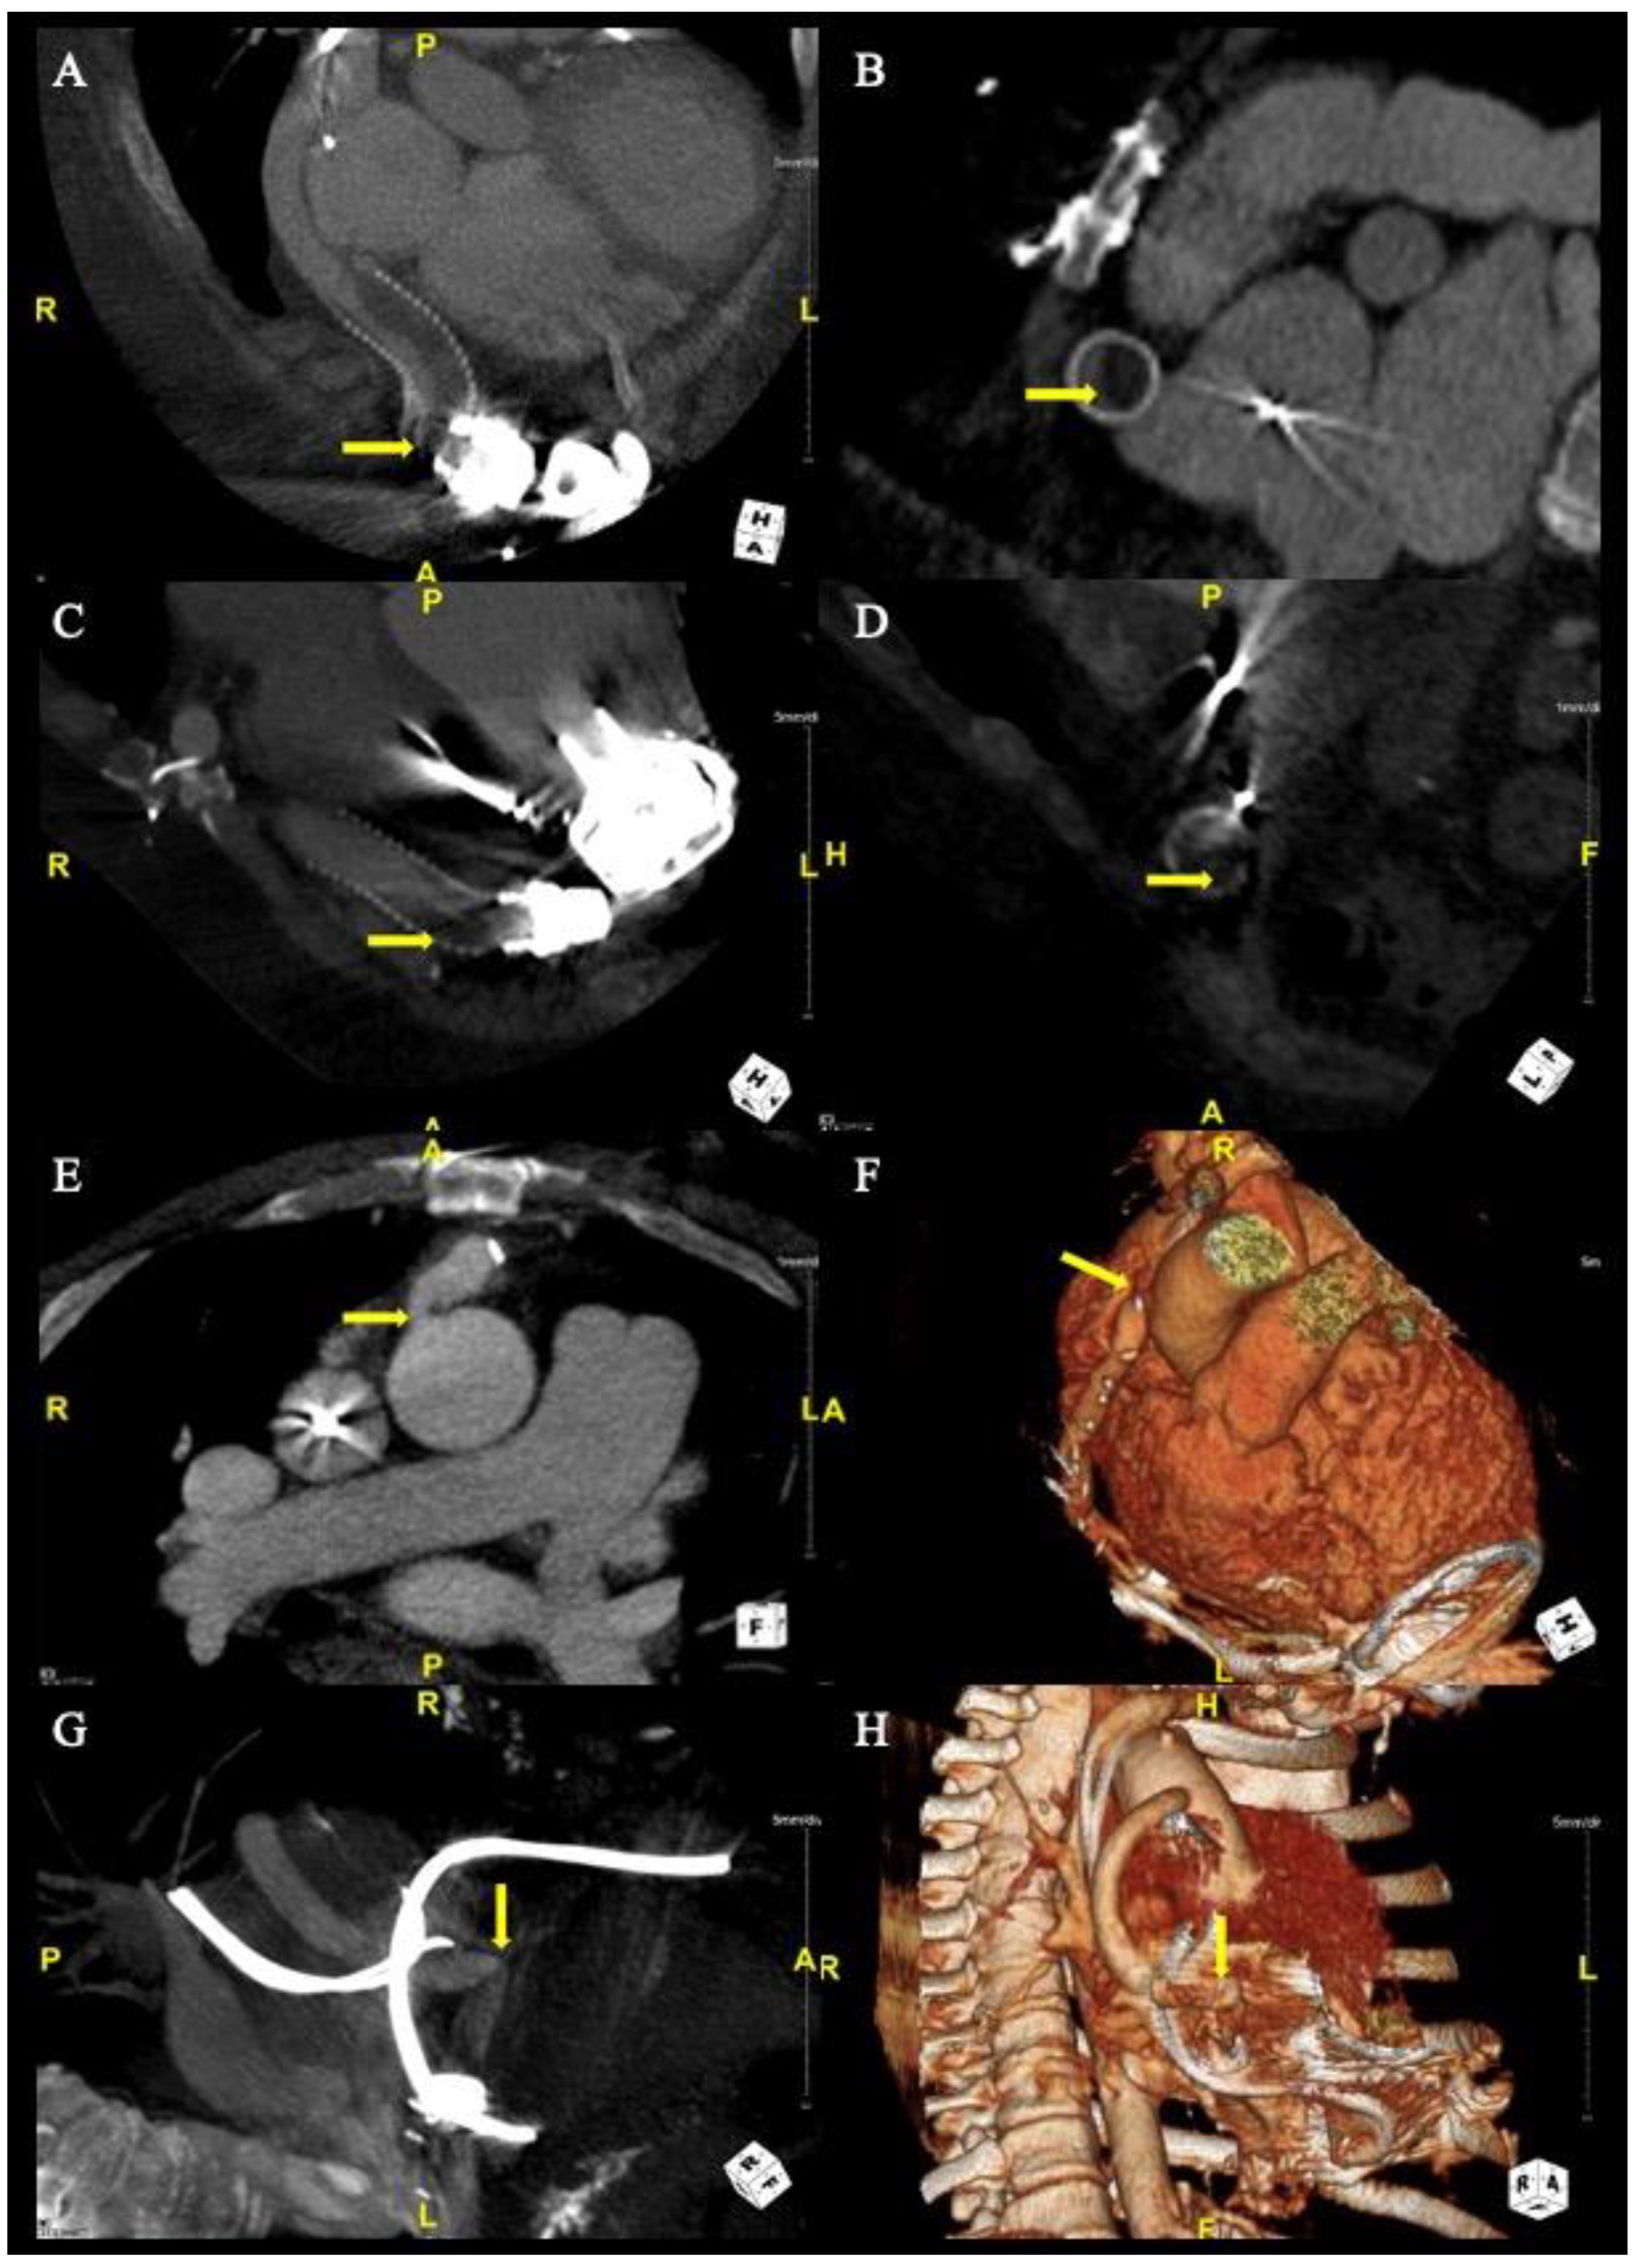

Figure 1.

Computed Tomography Angiography of Obstructions. For case 1, CTA (Panel A) demonstrates stenosis with bend relief disconnect and CTA (Panel B) demonstrates a partially occlusive thrombus. For case 5, CTAs (Panel C,D) demonstrate partially occlusive thrombus. For case 8, CTAs (Panel E,F) demonstrate ascending aorta anastomotic stenosis. For case 11, CTAs (Panel G,H) demonstrate outflow cannula kink.